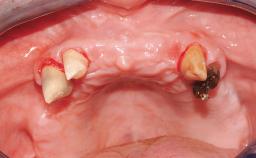

Conventional Loading of Six Implants in the Mandible and Final Restoration with a Full-Arch Metal-Ceramic FDP

A 68-year-old, completely edentulous male patient presented for evaluation and treatment options. He reported excellent general health and was taking no regular medication. He had been edentulous for approximately 12 years, having lost his teeth to periodontal disease and dental caries. The patient’s chief complaint was incompetent function. His secondary concerns included his appearance and the desire for a predictable outcome. He attributed his reduced functional capacity to his lower complete denture, which he described as poor. He was particularly concerned with the denture’s instability and poor fit. In general terms, he was satisfied with the maxillary complete prosthesis. The maxillary prosthesis was characterized by adequate retention, stability, and support, although the fit was considered less than ideal.

Case Type Edentulous Mandible

Jaw Mandible